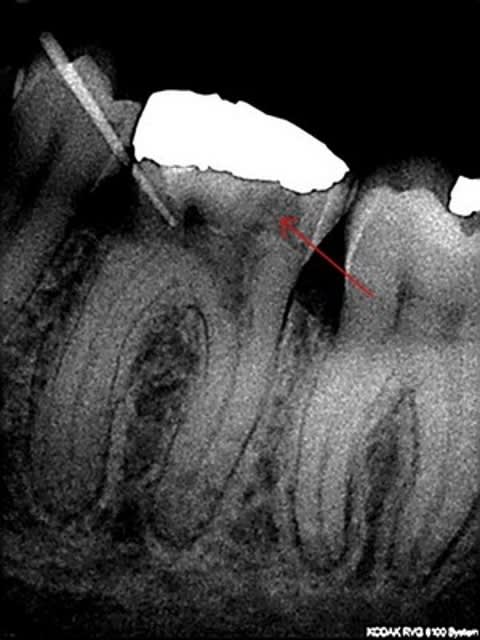

Je viens de recevoir il y a quelques minutes une patiente qui ressent une gêne au brossage au niveau de 36.

je pensais trouver un lésion d'usure liée au brossage , et je trouve un fistule située entre entre 36 et 35 en vestibulaire et coté 36, à 3 mm sous la gengive marginale.

présence d'un gros am ancien et assez large.

Diagnostic : fêlure liè à l'Amalgame et aux contraintes occlusales. on voit plusieurs début de fêlure au niveau de l'émail de la cupide mésio-vest, dont une qui plonge en sous gingival.(mais c'est pas trés net)

resorption cervicale ....

proablement résorption interne perforante.

effectivement sur la radio on voit cette image radio claire.

Ce qui m'a induit en erreur, c'est la vision de fêlure au niveau vestibulaire et le sondage en regard de la fistule.

marc, à quoi correspond cliniquement la zone radioclaire (flèche) ?

C'est une r2sorption interne perforante. Probablement pas un tissu carieux. Un processus inflammatoire chronique qui s'est emballe